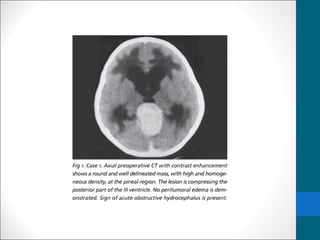

Computed Tomography

• Nonenhanced CT scans

• Typically demonstrate a slightly hyperattenuating

mass that engulfs a prominent calcified pineal gland.

• Contrast-enhanced CT scanning

• demonstrates homogeneous and intense

enhancement.

Computed Tomography •Nonenhanced CT scans • Typically demonstrate a slightly hyperattenuating mass that engulfs a prominent calcified pineal gland. • Contrast-enhanced CT scanning • demonstrates homogeneous and intense enhancement.

Axial, post-contrast CTdemonstrates an enhancing mass in the pineal region, which engulfs a calcified pineal gland